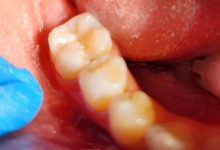

Clinica LUY ESTHETIC ART dispune de ultimele tehnologii in domeniul stomatologic si ofera solutia tratamentelor endodontice, pentru a incerca sa salveze un dinte care a fost distrus in proportii mari. Specialistii nostrii efectueaza acest tratament in mod corespunzator, pentru a evita aparitia altor complicatii ce implica interventii mai complexe: rezectia apicala sau riscul de a pierde dintele.

Stresul, fumatul, o igiena dentara precara, dar si modul de alimentatie duc la formarea cariilor. Acestea, netratate, favorizeaza aparitia infectiilor care vor dezvolta chisturi. Astfel de probleme se trateaza cu ajutorul tratamentului endodontic, zona respectiva fiind bine izolata pentru a preveni alte infectii. Atunci cand masurile nu sunt luate din timp, pulpa infectata moare si se formeaza chisturi la nivelul radacinii, iar interventia va deveni mai complexa.

Tratamentul endodontic este mult mai eficient si usor atunci cand bacteriile nu ajung pana in varful radacinii si nu apar chisturile.

La Clinica LUY ESTHETIC ART tratamentul endodontic poate fi efectuat pe durata mai multor sedinte, doar cand chisturile dezvoltate sunt medii. Tratamentul nu este dureros deoarece se realizeaza sub anestezie. Pe langa talent, cunostinte medicale, dar si meticulozitate, acest tratament, presupune folosirea unei aparaturi performante: